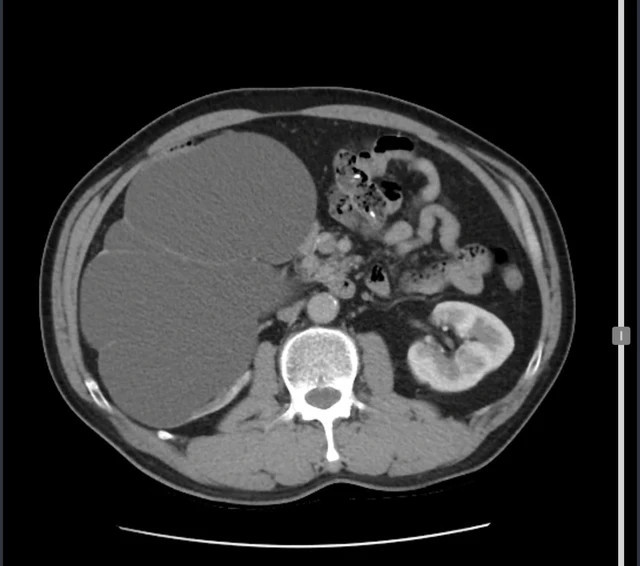

Cụ thể, Bệnh nhân đến viện trong trạng thái đau tức vùng hông phải, thấy rõ một khối nổi lên. Kết quả chụp CT bụng cho thấy thận phải của bệnh nhân ứ nước, kích thước 20x15cm, gần bằng quả bưởi kèm sỏi niệu quản.

| Thận phải của bệnh nhân ứ nước, kích thước 20x15cm, gần bằng quả bưởi kèm sỏi niệu quản. Ảnh Sk&ĐS |